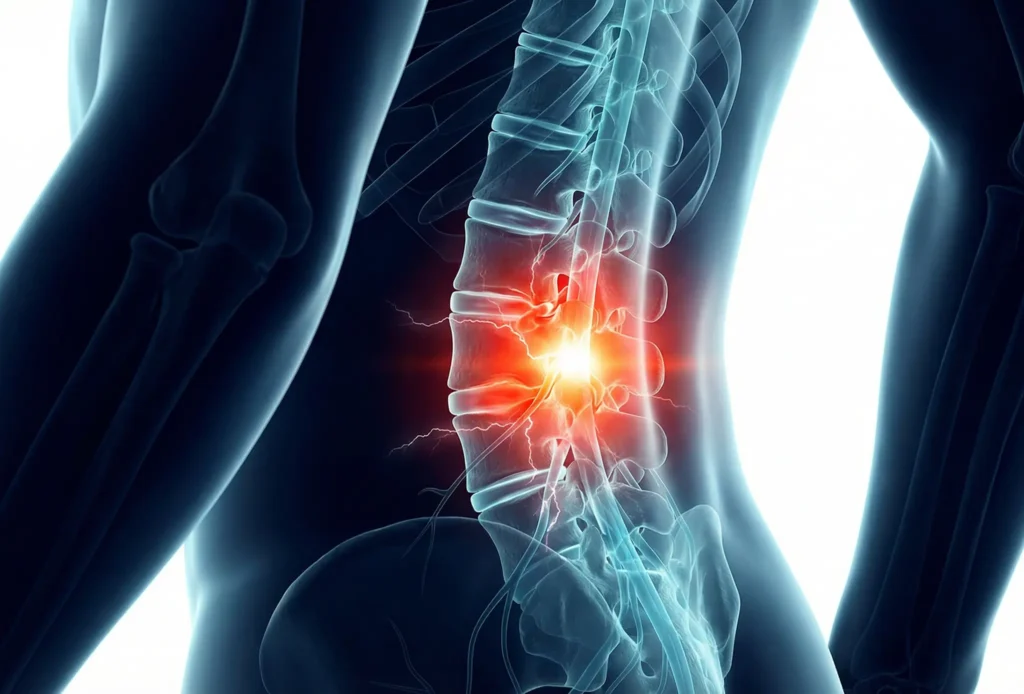

Lumbar Laminectomy / Decompression

When nerve compression causes leg pain, numbness, or weakness, decompression removes the pressure so nerves can recover, often without fusion.

- Spinal stenosis or disc herniation with radicular symptoms

How It Works

- Small posterior incisions are made

- Bone and ligament compressing the nerve are carefully removed